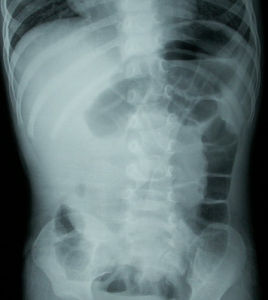

嬰幼兒腸套疊有典型症狀者一般診斷不困難。臨床上有陣發性腹痛、嘔吐、便血及腫塊四者存在即可確診。對只有陣發性腹痛和嘔吐的腸套疊早期,尚未出現血便,或晚期由於腹脹明顯觸不清腫塊的病例,應做直腸指檢,並進行空氣或鋇劑灌腸X線檢查,可及時作出正確診斷。結腸注氣或鋇劑X線檢查是一種簡便安全而可靠的診斷方法,不但可以及時作出正確診斷,同時也是較好的治療措施。